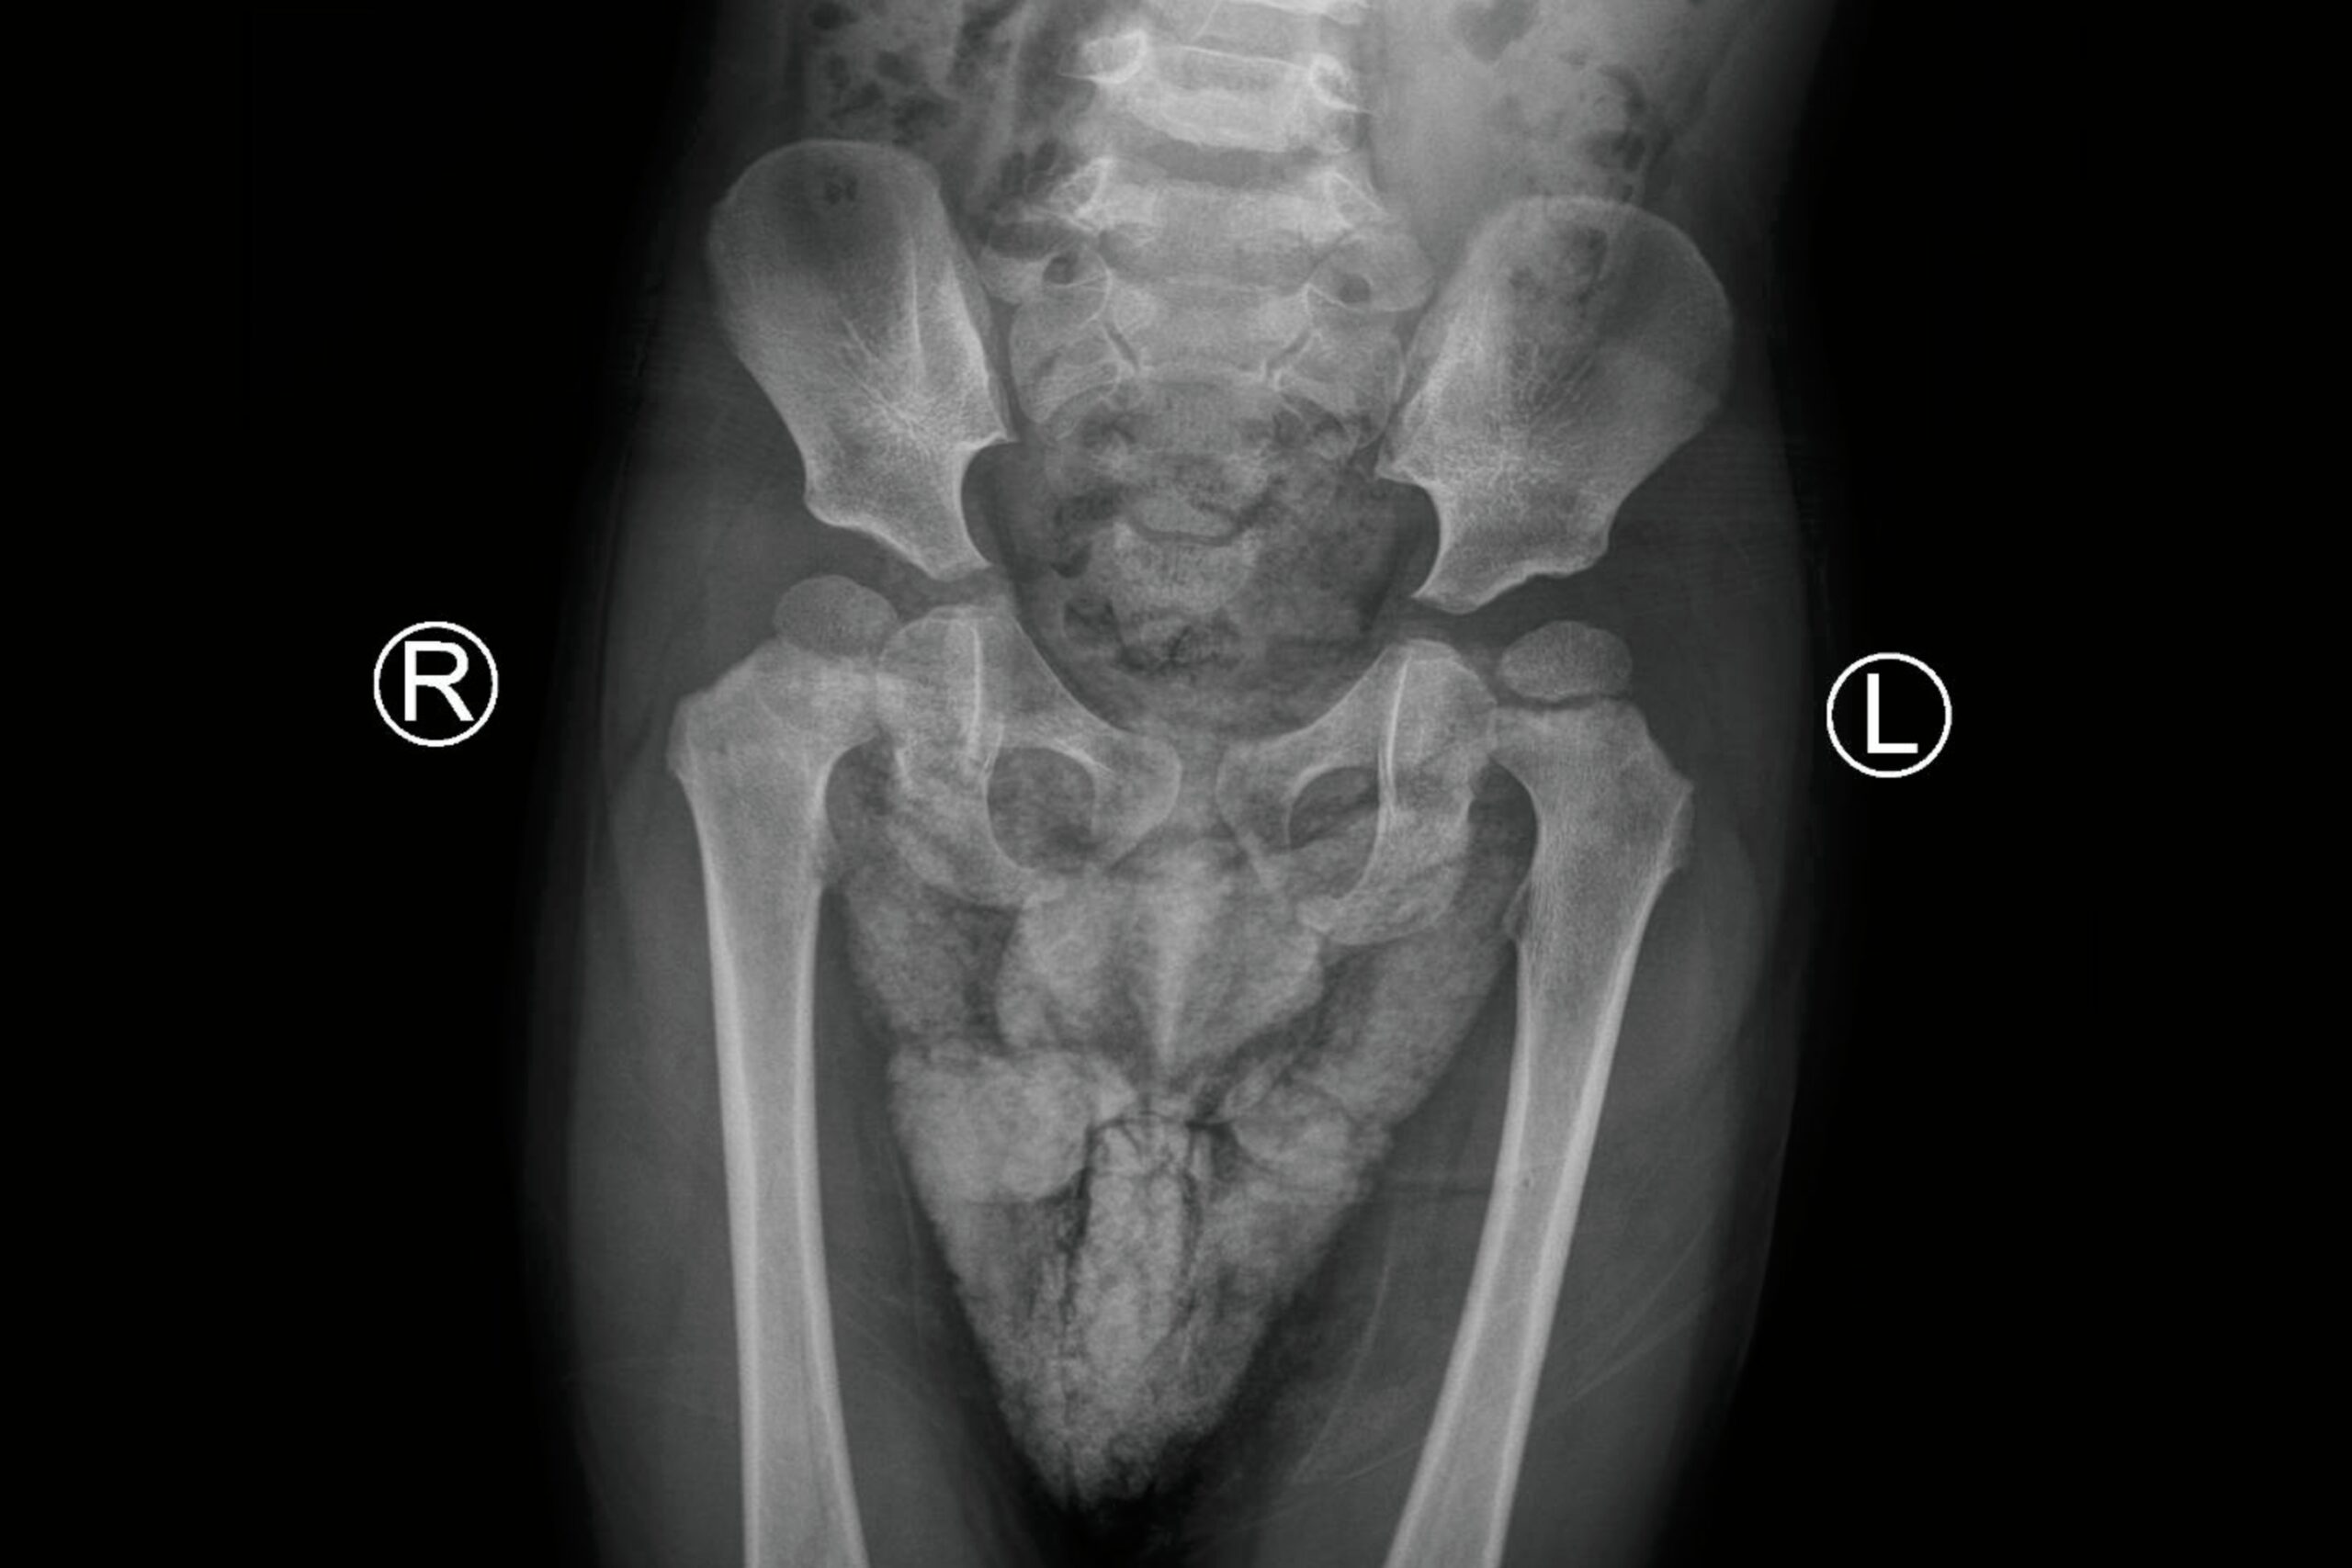

Por lo general, el médico puede sentir si algo está mal. El médico primero revisa las caderas de su bebé en el hospital después del nacimiento. Lo hacen empujando y tirando suavemente de los huesos del muslo del bebé para ver si están sueltos en la cavidad de la cadera. Puede ser necesario un ultrasonido para obtener una imagen de la cadera. Las radiografías se pueden tomar una vez que el bebé tenga 3 meses de edad.